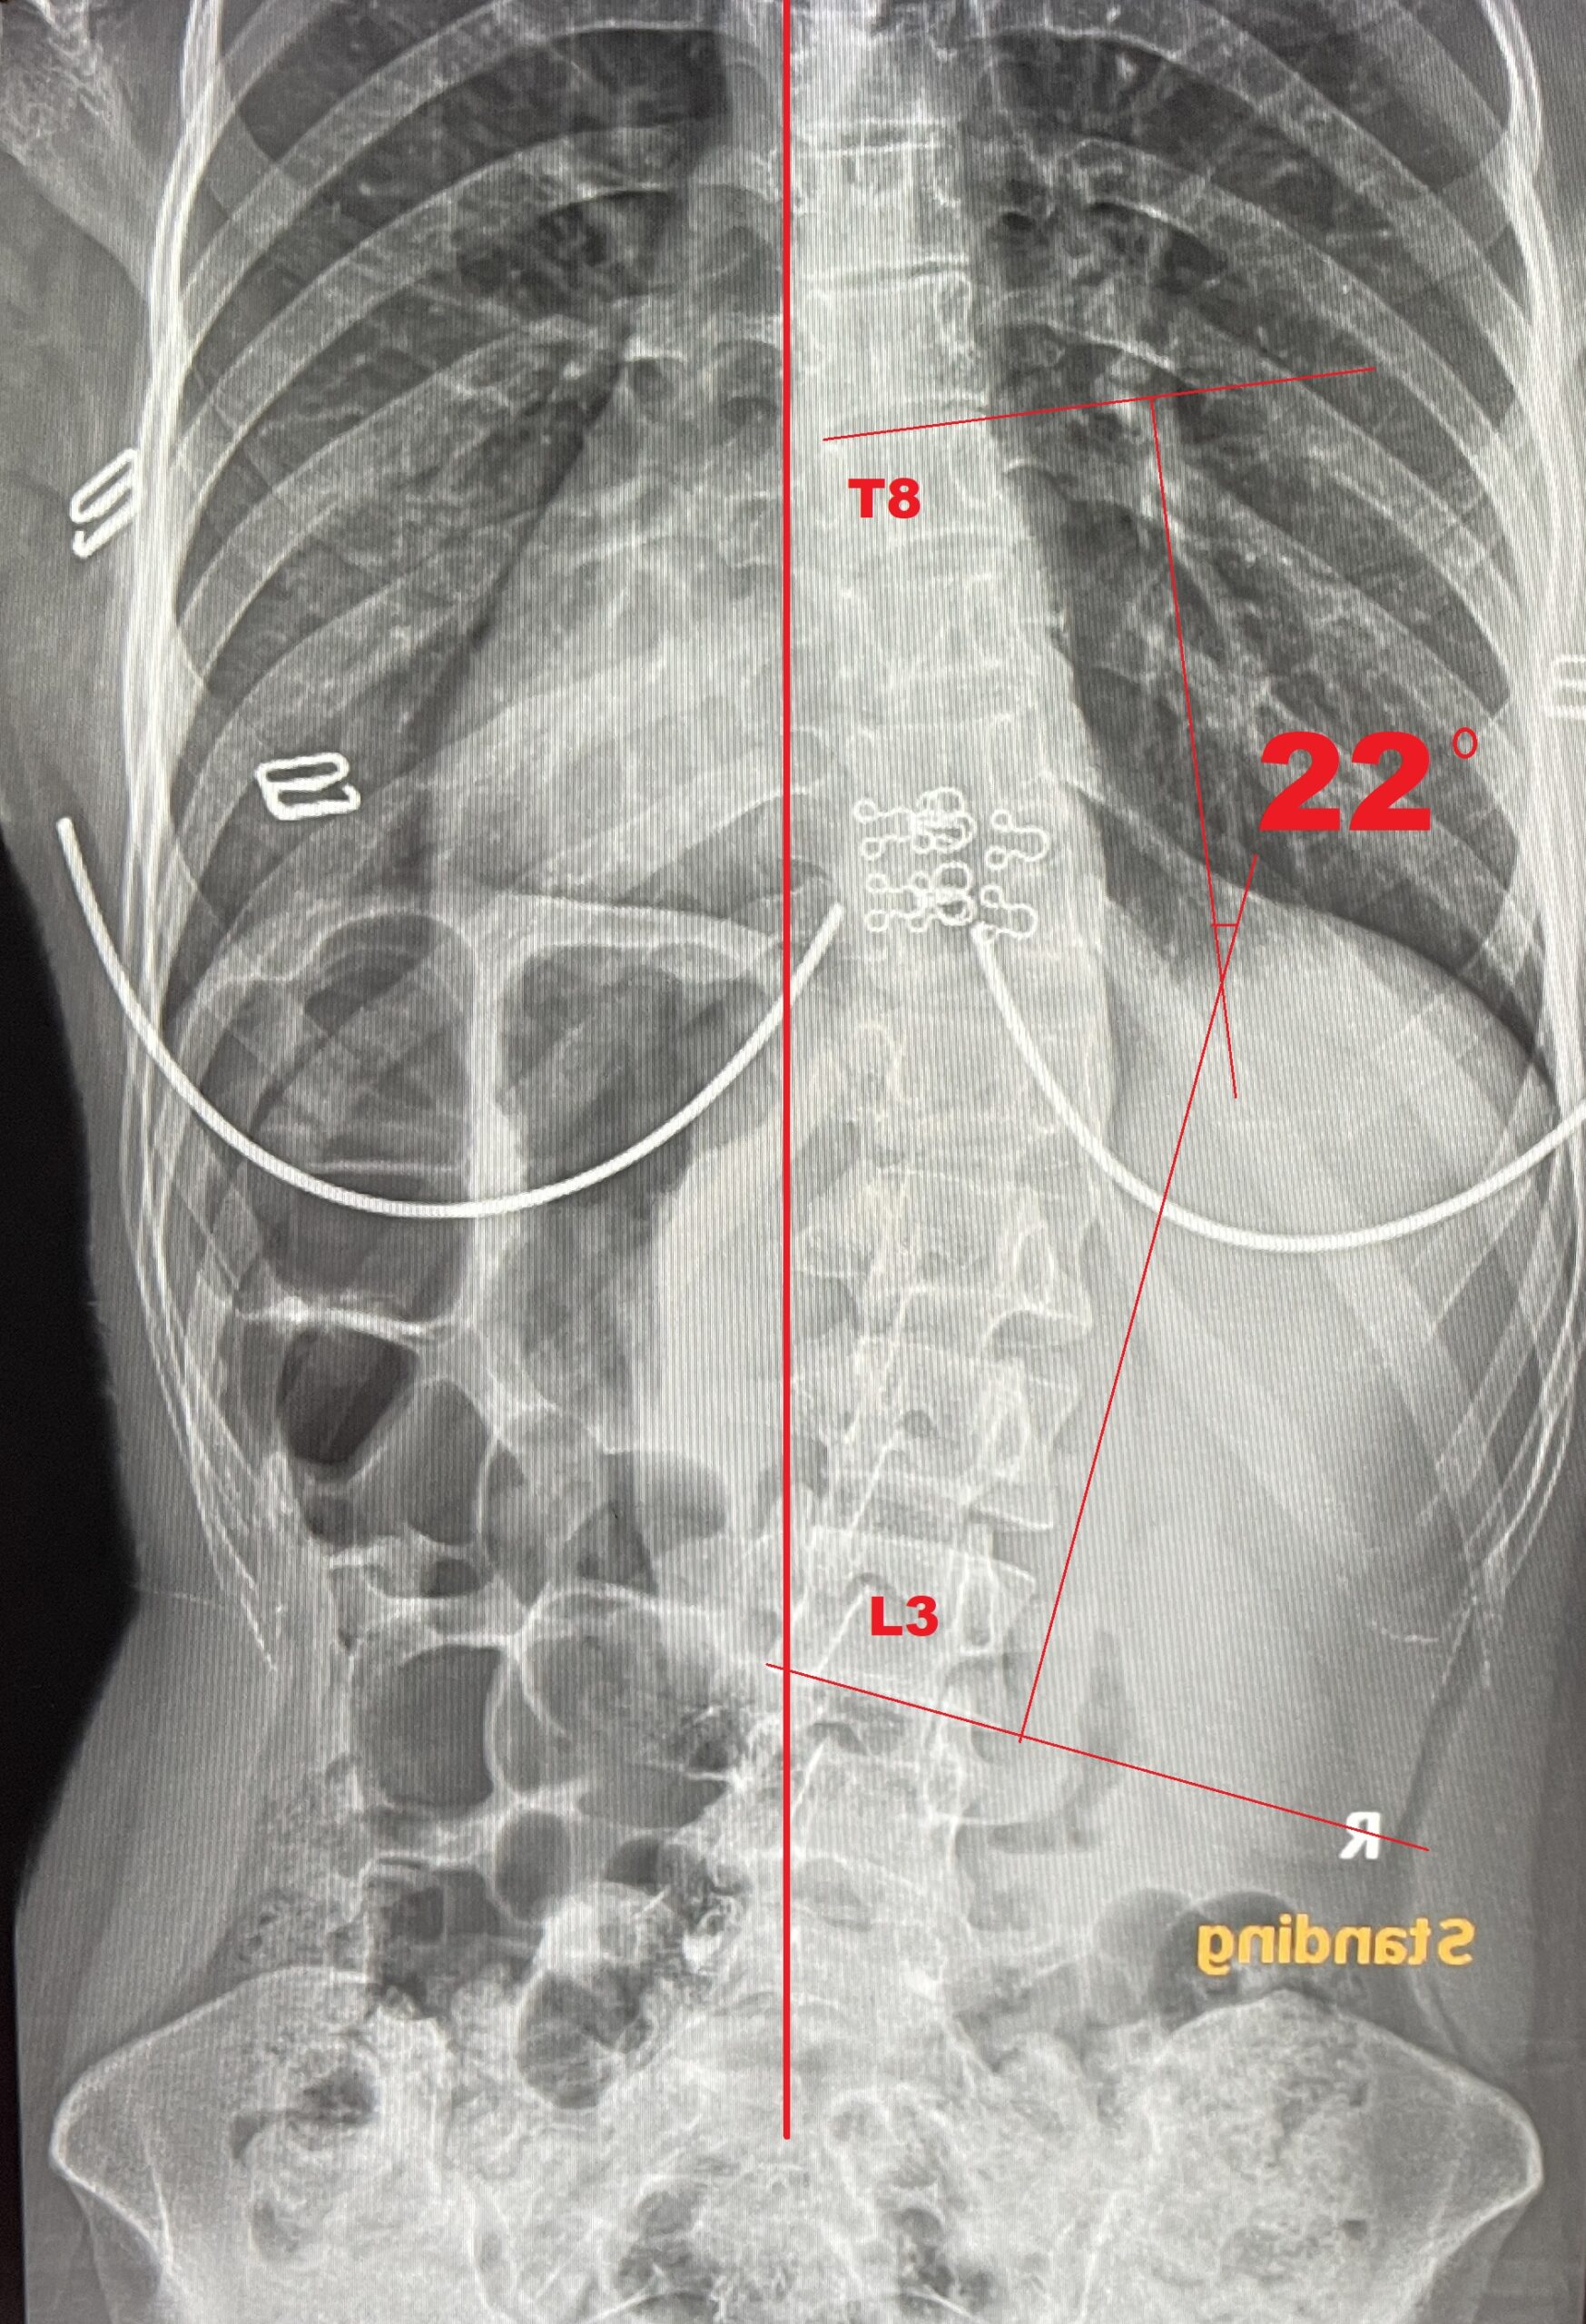

-治療期間: 14日間-

- 治療前: 側弯症カーブ 22°、痛みがあり、姿勢の悪化を感じていた

- 治療後: 側弯症カーブ 3°、痛み消失、体が軽くなり姿勢も大幅に改善

- 結果: 手術不要

Before

After